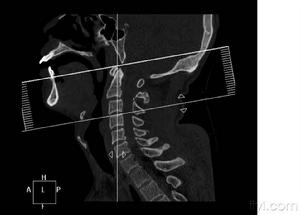

頸髓損傷X片臨床上通常可以通過X線顯示的頸椎骨折脫位的部位對頸髓損傷節段作出判斷,但有時頸椎的變化並不明顯,因此 需通過仔細檢查皮膚感覺障礙、肌肉運動障礙及反射的變化來確定。在解剖和功能的關係中,許多神經分布是交叉或重疊的,檢查時必須仔細加以辨認。有時甚至需經過反覆檢查,或從不同方向確定感覺障礙平面,才可獲得較準確的結論。頸3-4支配整個上頸部感覺,並表現為披肩狀分布的上胸部感覺。下位頸段損傷範圍需通過檢查上肢感覺分布來確定。